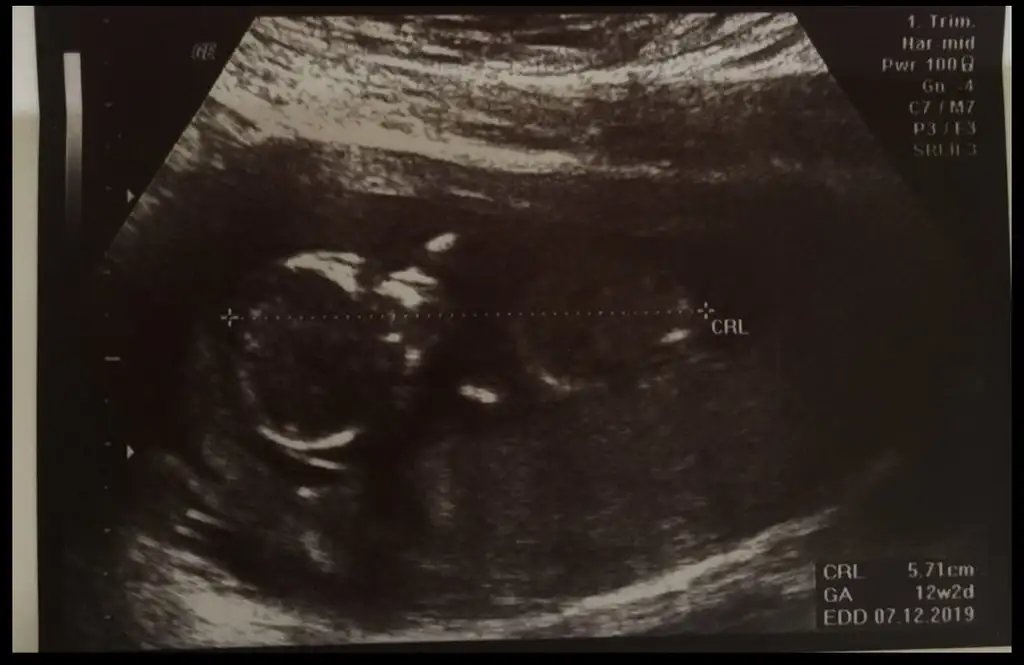

Nub yöntemine göre cinsiyet tahmini

BANADA rica etsem yorum yaparmısınız 10 haftalıgız ☺️☺️